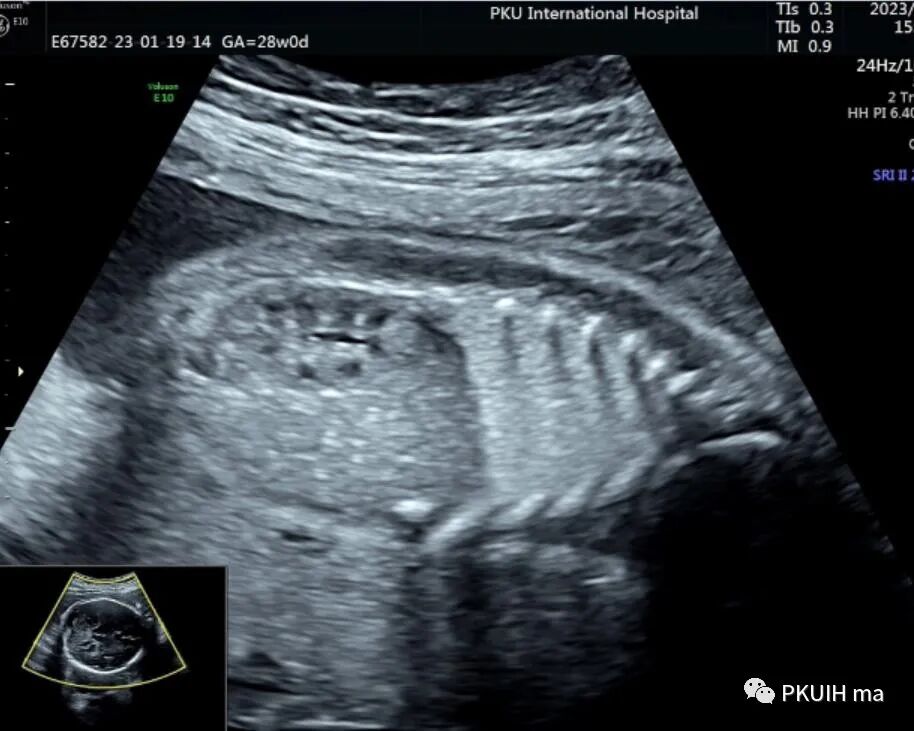

下图是一个28周胎儿正常肾的矢状面图像,肾位置正常,边界清晰,肾盂呈水平状,与脊柱方向近乎平行。